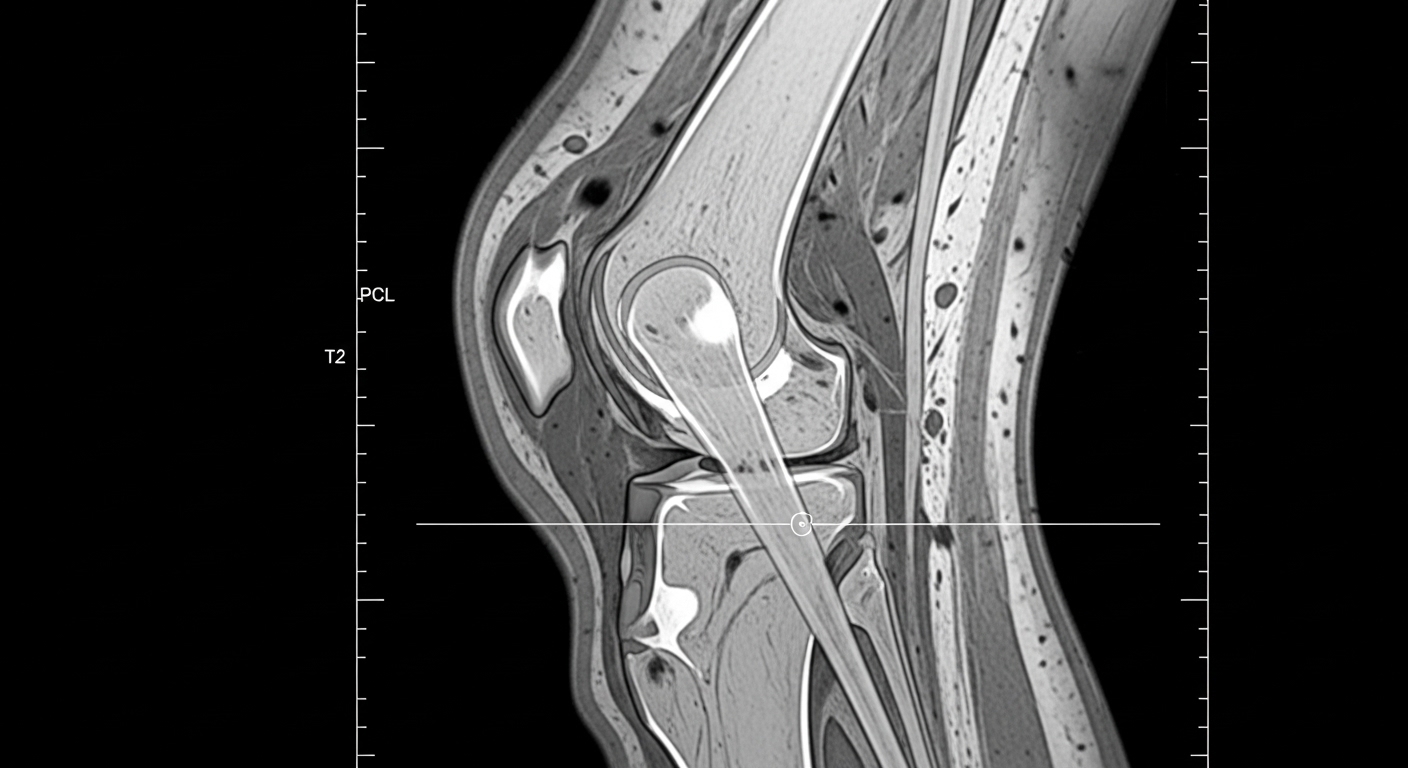

무릎 인공관절 수술은 연골이 심하게 닳아 일상생활이 어려울 때, 손상된 무릎 관절을 금속과 플라스틱 재질의 인공관절로 교체하는 수술이에요. 주로 퇴행성 관절염이 상당히 진행된 분들에게 권고된답니다.

수술 방식은 크게 두 가지로 나뉘어요. 전치환술(TKA)은 무릎 관절 전체를 인공관절로 바꾸는 방식이고, 부분치환술(PKA)은 손상된 한쪽 구획만 교체해요. 최근에는 로봇 보조 수술 방식도 많이 도입되어, 정밀도와 수명 면에서 기존 수술보다 개선된 결과를 보여주고 있어요.